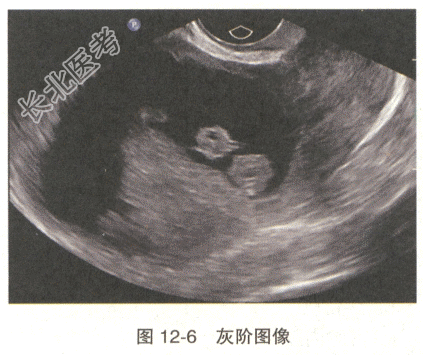

- 多项选择题3.经阴道超声检查示子宫增大,宫腔线分离, 宫腔内见不规则低回声,内部回声不均, 与子宫后壁肌层分界不清(图12-6),CDFI: 内部见较丰富血流信号,频谱为低阻血流, RI:0.32(图12-7)。最可能的诊断是